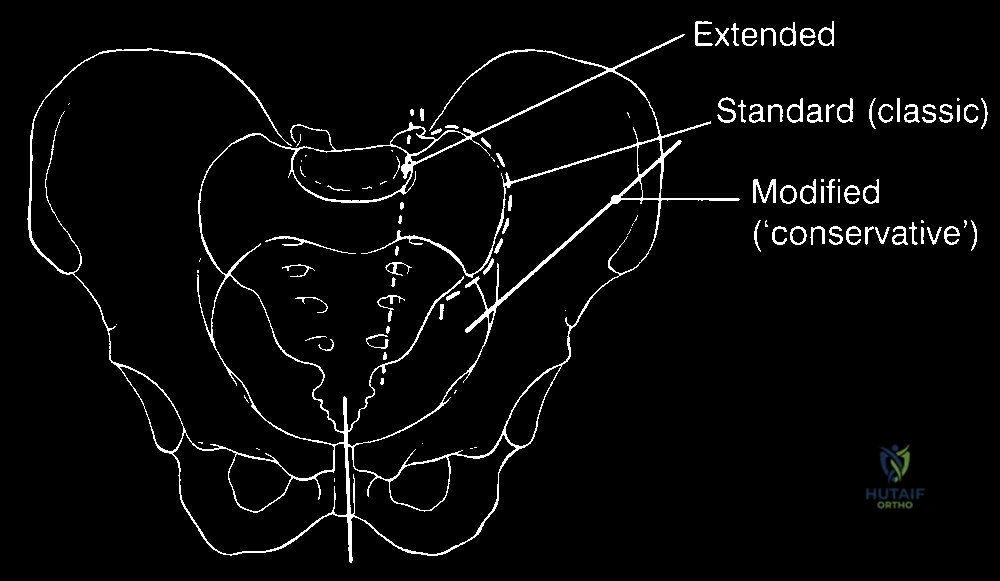

لماذا تُسمى هذه العملية بـ "بتر النصف الحوضي بالسديلة الخلفية"؟

عند إزالة نصف الحوض والطرف السفلي، يتبقى جرح مفتوح ضخم جداً في جانب الجسم. لا يمكن إغلاق هذا الجرح ببساطة. لذلك، يعتمد الجراح الماهر على تصميم هندسي تشريحي مسبق.

يقوم الدكتور هطيف برسم خطوط الشق الجراحي بحيث يتم الحفاظ على الجلد والعضلات الموجودة في الأرداف (الجهة الخلفية) - بشرط أن تكون خالية من الورم. هذه الأنسجة المحفوظة تُسمى "السديلة" (Flap). بعد إزالة العظام والورم، يتم طي هذه السديلة للأمام لتغطية الأعضاء الداخلية وتشكيل جدار قوي ووسادة نسيجية متينة.

يبدأ الدكتور هطيف بعمل شق جراحي أمامي يمتد فوق الرباط الأربي. الهدف الأول والأهم هو تحديد الأوعية الدموية الرئيسية (الشريان والوريد الحرقفي الأصلي أو الظاهر).

الخطوة الثالثة: الشق الخلفي ورفع السديلة

الخطوة الرابعة: قص العظام (Osteotomy) وفصل الحوض

باستخدام مناشير عظمية متقدمة، يتم فصل عظام الحوض عن العمود الفقري (عند المفصل العجزي الحرقفي) وفصلها من الأمام (عند الارتفاق العاني). يتطلب هذا دقة متناهية لضمان استئصال الورم بالكامل دون المساس بالأعضاء الداخلية في الحوض (مثل المثانة والمستقيم).